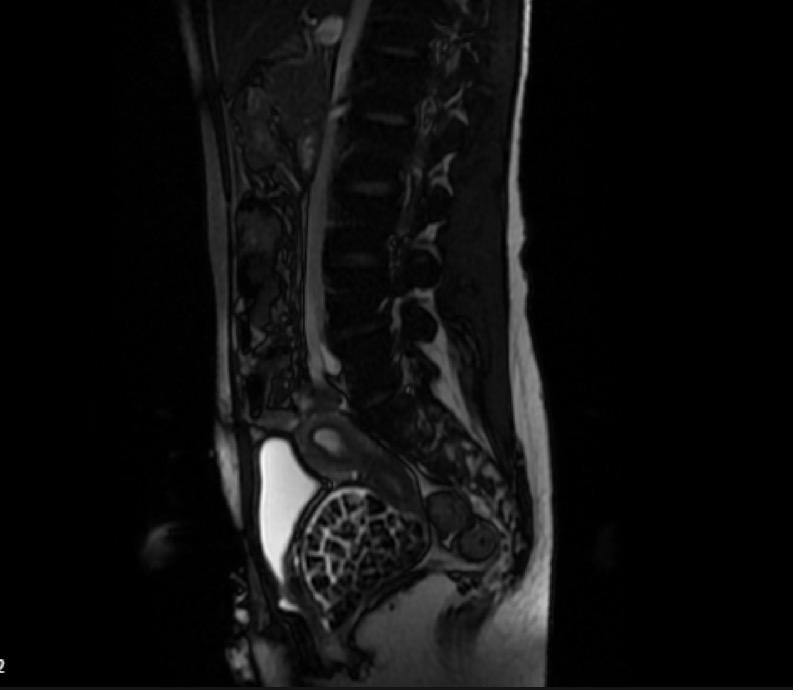

Hastasının durumuna yönelik konuşan Üroloji Uzmanı Doç. Dr. Erkan Erkan, "Hastamızın 2004 yılında doğduğunu ardından doğar doğmaz ekstrofi vezika dediğimiz 50 binde bir görülen bir anomaliden dolayı art arda ameliyatlar geçirdiğini öğrendik. 10 yaşında yine bir ameliyat geçirmişti, gerekli görüntüleme ve tetkiklerimizi yaptırdık. Normalde mesanesinin olması gereken yerin hemen arka kısmında taşlarla dolu bir kese olduğunu gördük, bunun üzerine ek görüntülemeler; MR çektirdik. Hastamız çelişkili açıklamalar almıştı, kendi radyolojik kliniğimiz ve edindiğimiz konsültasyonlarda taşların mesanede değil vajinal boşlukta oluştuğunu düşündük, bir planlama yaptık. Kadın doğum hocamızın da çabasıyla taşları tamamen temizledik ardından ileride normal bir hayat sürmesi bakımından oraya plastik cerrahi yaptık. 287 adet taş çıkardık, pratikte gerçekten görünce çok şaşırdık çünkü bu aynı zamanda literatürde çok nadir görülen bir olay. Biz ameliyata hazırlanırken de teorik olarak biraz araştırdık. Literatürde gördüğümüz kadarıyla buna benzer bu tanıma uyan bir vaka vardı. Literatürde sanırım yayınlanmış 2’nci vaka olacak. Farkındalık çok önemli, bilinçli bir hastamız vardı. Doğumsal anomaliyle doğan çocuklarımızda ileride bunlara bağlı bazı sıkıntılar çıkabileceğinin öngörülmesi lazım. İlgili tedavilerini alsalar bile düzenli takiplere gelmeleri gerekiyor. İleride eğer dikkat etmezse ki zannetmiyorum, tekrarlayabilir. Bu rahatsızlık ekstrofi vezikal epispadias durumu çok nadir bir durum" dedi.

"Tüm vajenin taşlarla dolu olduğunu gördük"Genç kızın uzun süredir devam eden karın ağrısı olduğunu söyleyerek sözlerine başlayan Jinekolojik Onkoloji Uzmanı Op. Dr. Emin Erhan Dönmez, "Mesane taşları olduğu düşünülerek daha büyük bir hastaneye refere edilmiş. Aramızda mini bir konsey yaparak muayene ettik. Vajen bir hazne görevi görerek orada durağan bir idrar, uzun süre beklediği için idrar içindeki minerallerde çökerek taşlar oluşmuş. Mesanedeki idrarın vajene akmış olabileceği ve vajende göllenen idrar nedeniyle taşların burada oluşacağını düşündük, ameliyatımızı planladık. Ameliyata tanı amaçlı girmiştik, sistoskopi (Mesane gibi idrar yollarını kapsayan kısımlardaki rahatsızlıkların teşhis ve tedavisinde kullanılan endoskopik bir yöntem) dediğimiz ameliyatı Erkan Hocam ile birlikte gerçekleştirdik. Önce mesaneyi bir görüntüledik, mesane tabanına yaklaşık 2-3 cm’lik bir alandan vajene fistülize olduğunu gördük. Mesaneden vajene geçtiğimiz esnada tüm vajenin taşlarla dolu olduğunu gördük. Tanı amacıyla girdiğimiz ameliyatta her şey de olağan gittiği için tedaviye geçtik. Taşların çıkabileceği kadar bir genişlik sağladık. Daha sonra yaklaşık en büyüğü 2,5 cm boyutlarında olan, irili ufaklı 287 tane taşı ameliyat esnasında çıkarmış olduk. Taşların tekrarlamaması için idrarın göllenmemesi, en azından dışarıya rahatça boşalabilmesi için vajinal rekonstrüksiyonu sağladık. Ameliyatta da herhangi bir problem yaşamadık. Literatürü Erkan Hocam ile birlikte değerlendirmiştik. Primer olarak vajende birikmiş olan bu kadar çok sayıda taşla ilgili bir makale görmedik, rastlamadık" dedi.